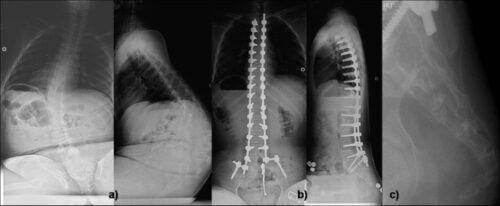

يتم أيضًا استخدام الأشعة السينية من الأمام والجانب لتحديد درجة الاعوجاج، وقد يشمل التشخيص المتقدم:

الجراحة: دمج الفقرات (Spinal Fusion)

عند تفاقم الانحناء أو تأثيره على الجلوس والتنفس، يوصى بـ جراحة دمج الفقرات. في هذه العملية، يُستخدم نظام من القضبان والمسامير المعدنية لتقويم العمود الفقري وتثبيته، وتستغرق فترة التئام الفقرات عادةً من 6 إلى 12 شهرًا.

أهداف الجراحة:

تثبيت العمود الفقري ومنع زيادة الانحناء.

تحسين توازن الحوض والعمود الفقري، خصوصًا للأطفال غير القادرين على المشي.

استعادة القدرة على الجلوس بشكل مستقيم.

تحسين أو الحفاظ على وظائف الرئة.

عادةً ما تشمل الجراحة جزءًا أطول من العمود الفقري مقارنة بأنواع الاعوجاج الأخرى، وتُجرى في سن مبكر بسبب سرعة تطور الحالة.